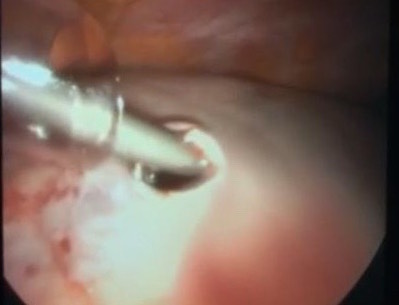

Laparoscopic approach for huge benign ovarian cyst in woman with history of previous 5 laparotomies (including 4 cesarean section)

An adnexal mass (mass of the ovary, fallopian tube, or surrounding connective tissues) is a common gynecologic problem. In the United States, it is estimated that there is a 5 to 10% lifetime risk for women undergoing surgery for a suspected ovarian neoplasm. Adnexal masses may be found in females of all ages, from fetuses to older adults, and there are a wide variety of types of masses. Today, the surgical treatment has become more conservative and less invasive; hence, a laparoscopic approach in the presence of benign cysts has become a golden standard. In the past, patients with previous abdominal surgery were discouraged from undergoing laparoscopic surgery because of its increased risk of bowel injury caused by needle and trocar insertion. Complications occur two times more frequently in patients with previous laparotomy in a study of long series. The potential risk for injury of organs adherent to the abdominal wall during veress needle or trocar insertion as well as the necessity for adhesiolysis and its attendant complications are the two major specific problems constraining surgeons from performing laparoscopic cystectomy/ oophorectomy for patients with previous abdominal surgery. Herein, we report a case of a 32-year-old woman P4 + 2 with history of previous four cesarean section and a following laparotomy for interval sterilization presented to our clinic with abdominal mass, discovered by ultrasound scan, managed by a laparoscopic approach.